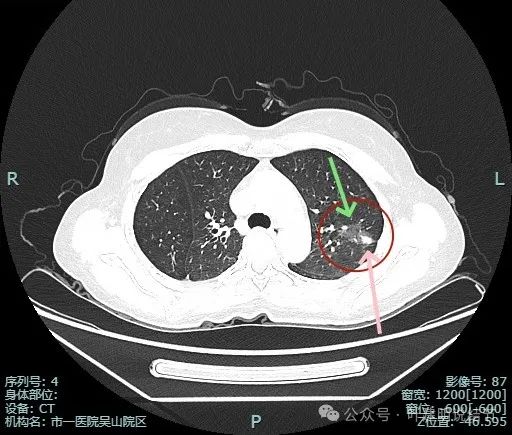

这种样子的混合磨玻璃阴影可直接切肺叶,甚至不必穿刺或活检,太典型了!

病史摘要:主诉发现肺占位半月余,复查胸部CT显示左肺上叶实性类结节影,患者从内科转入,内科已穿刺活检明确为恶性。诊疗过程:体格检查未提及。辅助检查方面,PET-CT 示左上叶尖后段占位,葡萄糖代谢增高,考虑恶性病变可能性大。影像显示病灶为混合密度,有胸膜牵拉、血管增粗等典型浸润性癌表现。杭州市第一

明明典型浸润性癌影像表现病理结果却是原位癌,原位癌也可表现为混合密度?

病史摘要:患者 3 个月前社区体检发现肺结节,就诊时医生考虑左上病灶基本为肺癌且倾向浸润性,因首次发现,建议口服抗炎 10 - 12 天,间隔 3 个月复查。此次复查无吸收好转及明显进展,拟手术治疗。诊疗过程:体格检查未提及。影像检查显示左上叶胸膜下混合密度结节,有血管弯征、胸膜牵拉等诸多恶性特征,下叶有次病灶。临床考虑左上叶病灶恶性且浸润性癌可能性大,建议手术。术中快速切片报腺癌